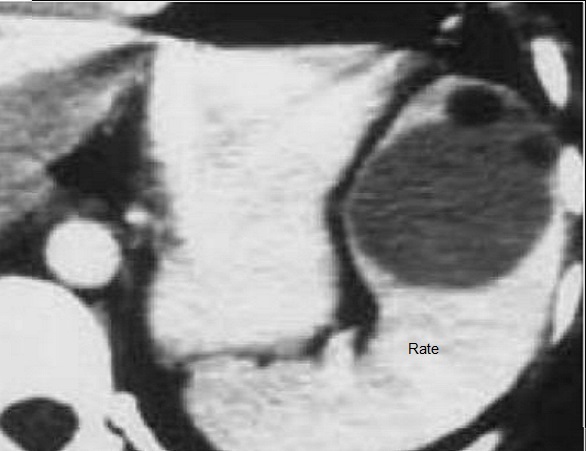

Une autre cas de rate

surnumeraire avec la rate secondaire a petite taille

pre-splenique ( fléche rouge ) |